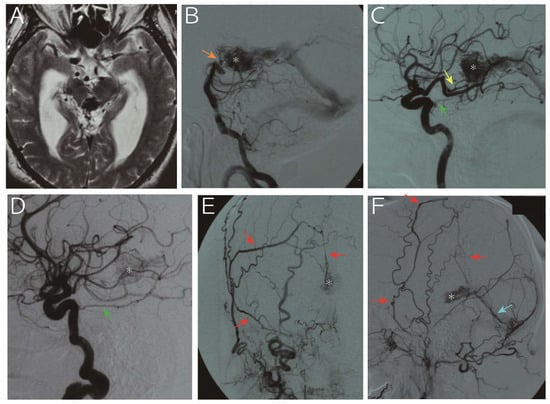

| 1 | 65, M | Hydrocephalus | 9.4 mL | MPChA, BA perforators | Tentorial a., MMA, PMA | VG | 153 mo | Died due to hemorrhage |

| 2 | 62, M | Seizure | 1.4 mL | MPChA, PCA perforators, pericallosal a. | Tentorial a. | VG | 255 mo | Alive, nidus obliteration |

| 3 | 68, M | Hydrocephalus | 0.9 mL | MPChA, PCA perforators | N/A | VG | 137 mo | Alive, nidus shrinkage |

| 4 | 31, F | Hydrocephalus and hemorrhage † | 12.2 mL | MPChA, PCA perforators | Tentorial a (N/A for the other ECA feeders) | VG | 38 mo | Alive, nidus shrinkage |

| 5 | 63, F | Headache | 2.3 mL | MPChA, PCA perforators, BA perforators | Tentorial a, MMA, PMA | VG | 47 mo | Alive, nidus shrinkage |

| 6 | 62, M | Hemorrhage | 1.2 mL | MPChA, BA perforators | Tentorial a, ILT | VG, superior vermian vein | 23 mo | Alive, nidus shrinkage |

| 7 | 55, M | Hemorrhage from flow-related AN | 1.6 mL | MPChA, pericallosal a. | ILT, PMA | VG, superior vermian vein | 12 mo | Alive, nidus shrinkage |

| 8 | 76, M | Hemorrhage | 1.7 mL | MPChA, PCA perforators | Tentorial a. | VG | 4 mo | Alive |